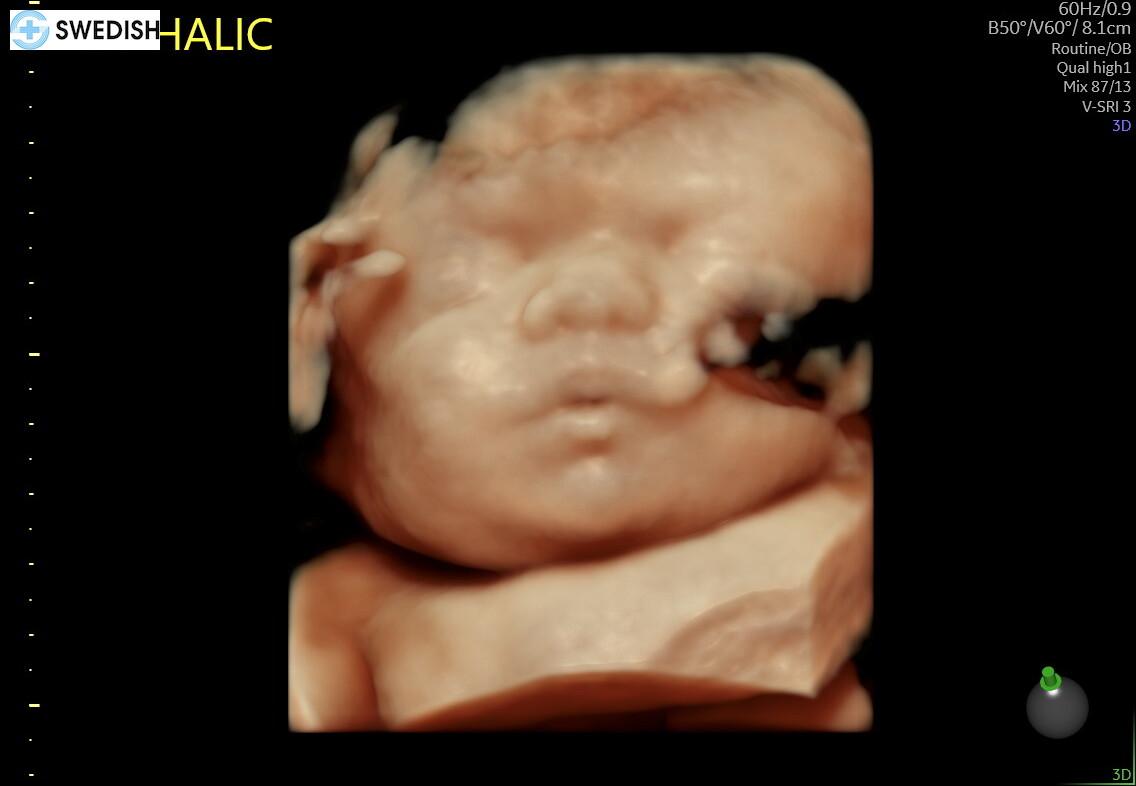

I was saddened when I heard the news of Sol's passing. You were loved immensely even before you arrived. If it is possible to live a lifetime in one day, Sol, you managed to do so. You left a big footprint on a lot of hearts. Your light was too bright for this world. We’ll look for you when we gaze at the stars in the heavens. Wish we could have met. Love you, your Great-Grand Aunt Frances  and your Great-Grand Uncle John Wraspir.